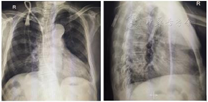

诊治经过:入院后患者家属放弃上肢AVF和移植物动静脉内瘘(arteriovenous graft,AVG),要求置入TCC作为长期透析血管通路。患者有反复右颈内静脉置管史,彩超探查右颈内静脉已闭塞,且患者有临时导管拔除史,故于2021年3月20日在B超引导下行右颈外静脉TCC置管术:B超引导下探寻右颈外静脉,置入导丝,用扩张器扩张皮下组织,切开皮肤2 cm,分离周围组织,暴露右颈外静脉,定位隧道出口于第三胸椎右侧距脊柱5 cm处,切开皮肤1 cm,分离皮下组织,置入带涤纶套套管(14.5 F, 50 cm, Palindrome; Medtronic, Minneapolis, MN),沿导丝置入撕脱鞘,后沿撕脱鞘置入导管于右颈外静脉,回抽导管动静脉端回血顺利,遂用肝素生理盐水封管,缝合切口,固定导管,无菌辅料包扎固定,患者无不适(图1)。血液透析流量达200~250 ml/min,X片显示导管位置见图2,观察2 d后出院至当地医院顺利透析。

诊治经过:入院后经彩超评估,患者周身外周血管耗竭,且血压偏低,年纪较大,故选择原位更换带涤纶套管,但因患者合并有认知障碍,有导管拔出史,不能配合侧卧位透析,故定位隧道出口于右侧肩峰处。导丝沿原长期导管置入右颈内静脉,拔出原透析导管,分离隧道处皮下组织,置入带涤纶套套管,沿导丝放入撕脱鞘,后沿撕脱鞘置入导管于右颈内静脉,回抽导管动静脉端回血顺利,遂用肝素生理盐水封管,缝合切口,固定导管,无菌辅料包扎固定,患者无不适(图3)。当日透析流量约200~230 ml/min,透析时患者保持平卧,导管动静脉接头可置于肩部,透析结束导管包扎固定于后背,该患者返回至当地医院规律透析。